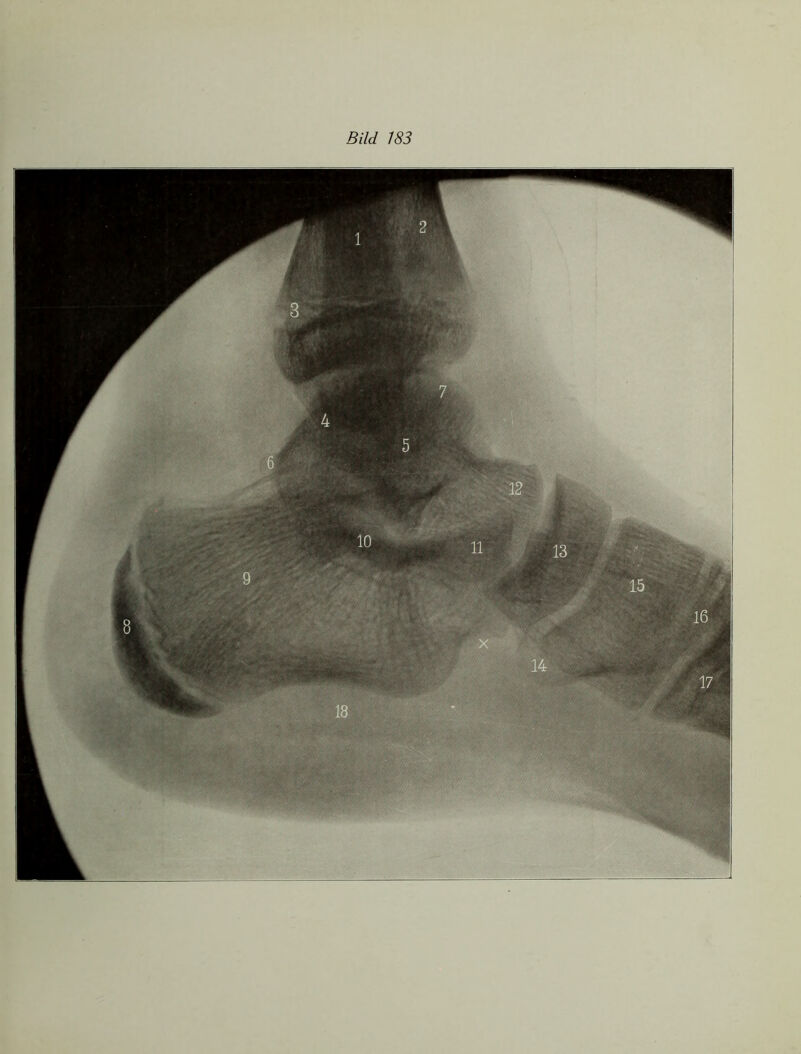

Atlas typischer Röntgenbilder vom normalen Menschen : ausgewählt und erklärt nach chirurgisch-praktischen Gesichtspunkten, mit Berücksichtigung der Varietäten und Fehlerquellen, sowie der Aufnahmetechnik / von Rudolf Grashey.

Credit: Atlas typischer Röntgenbilder vom normalen Menschen : ausgewählt und erklärt nach chirurgisch-praktischen Gesichtspunkten, mit Berücksichtigung der Varietäten und Fehlerquellen, sowie der Aufnahmetechnik / von Rudolf Grashey. Source: Wellcome Collection.